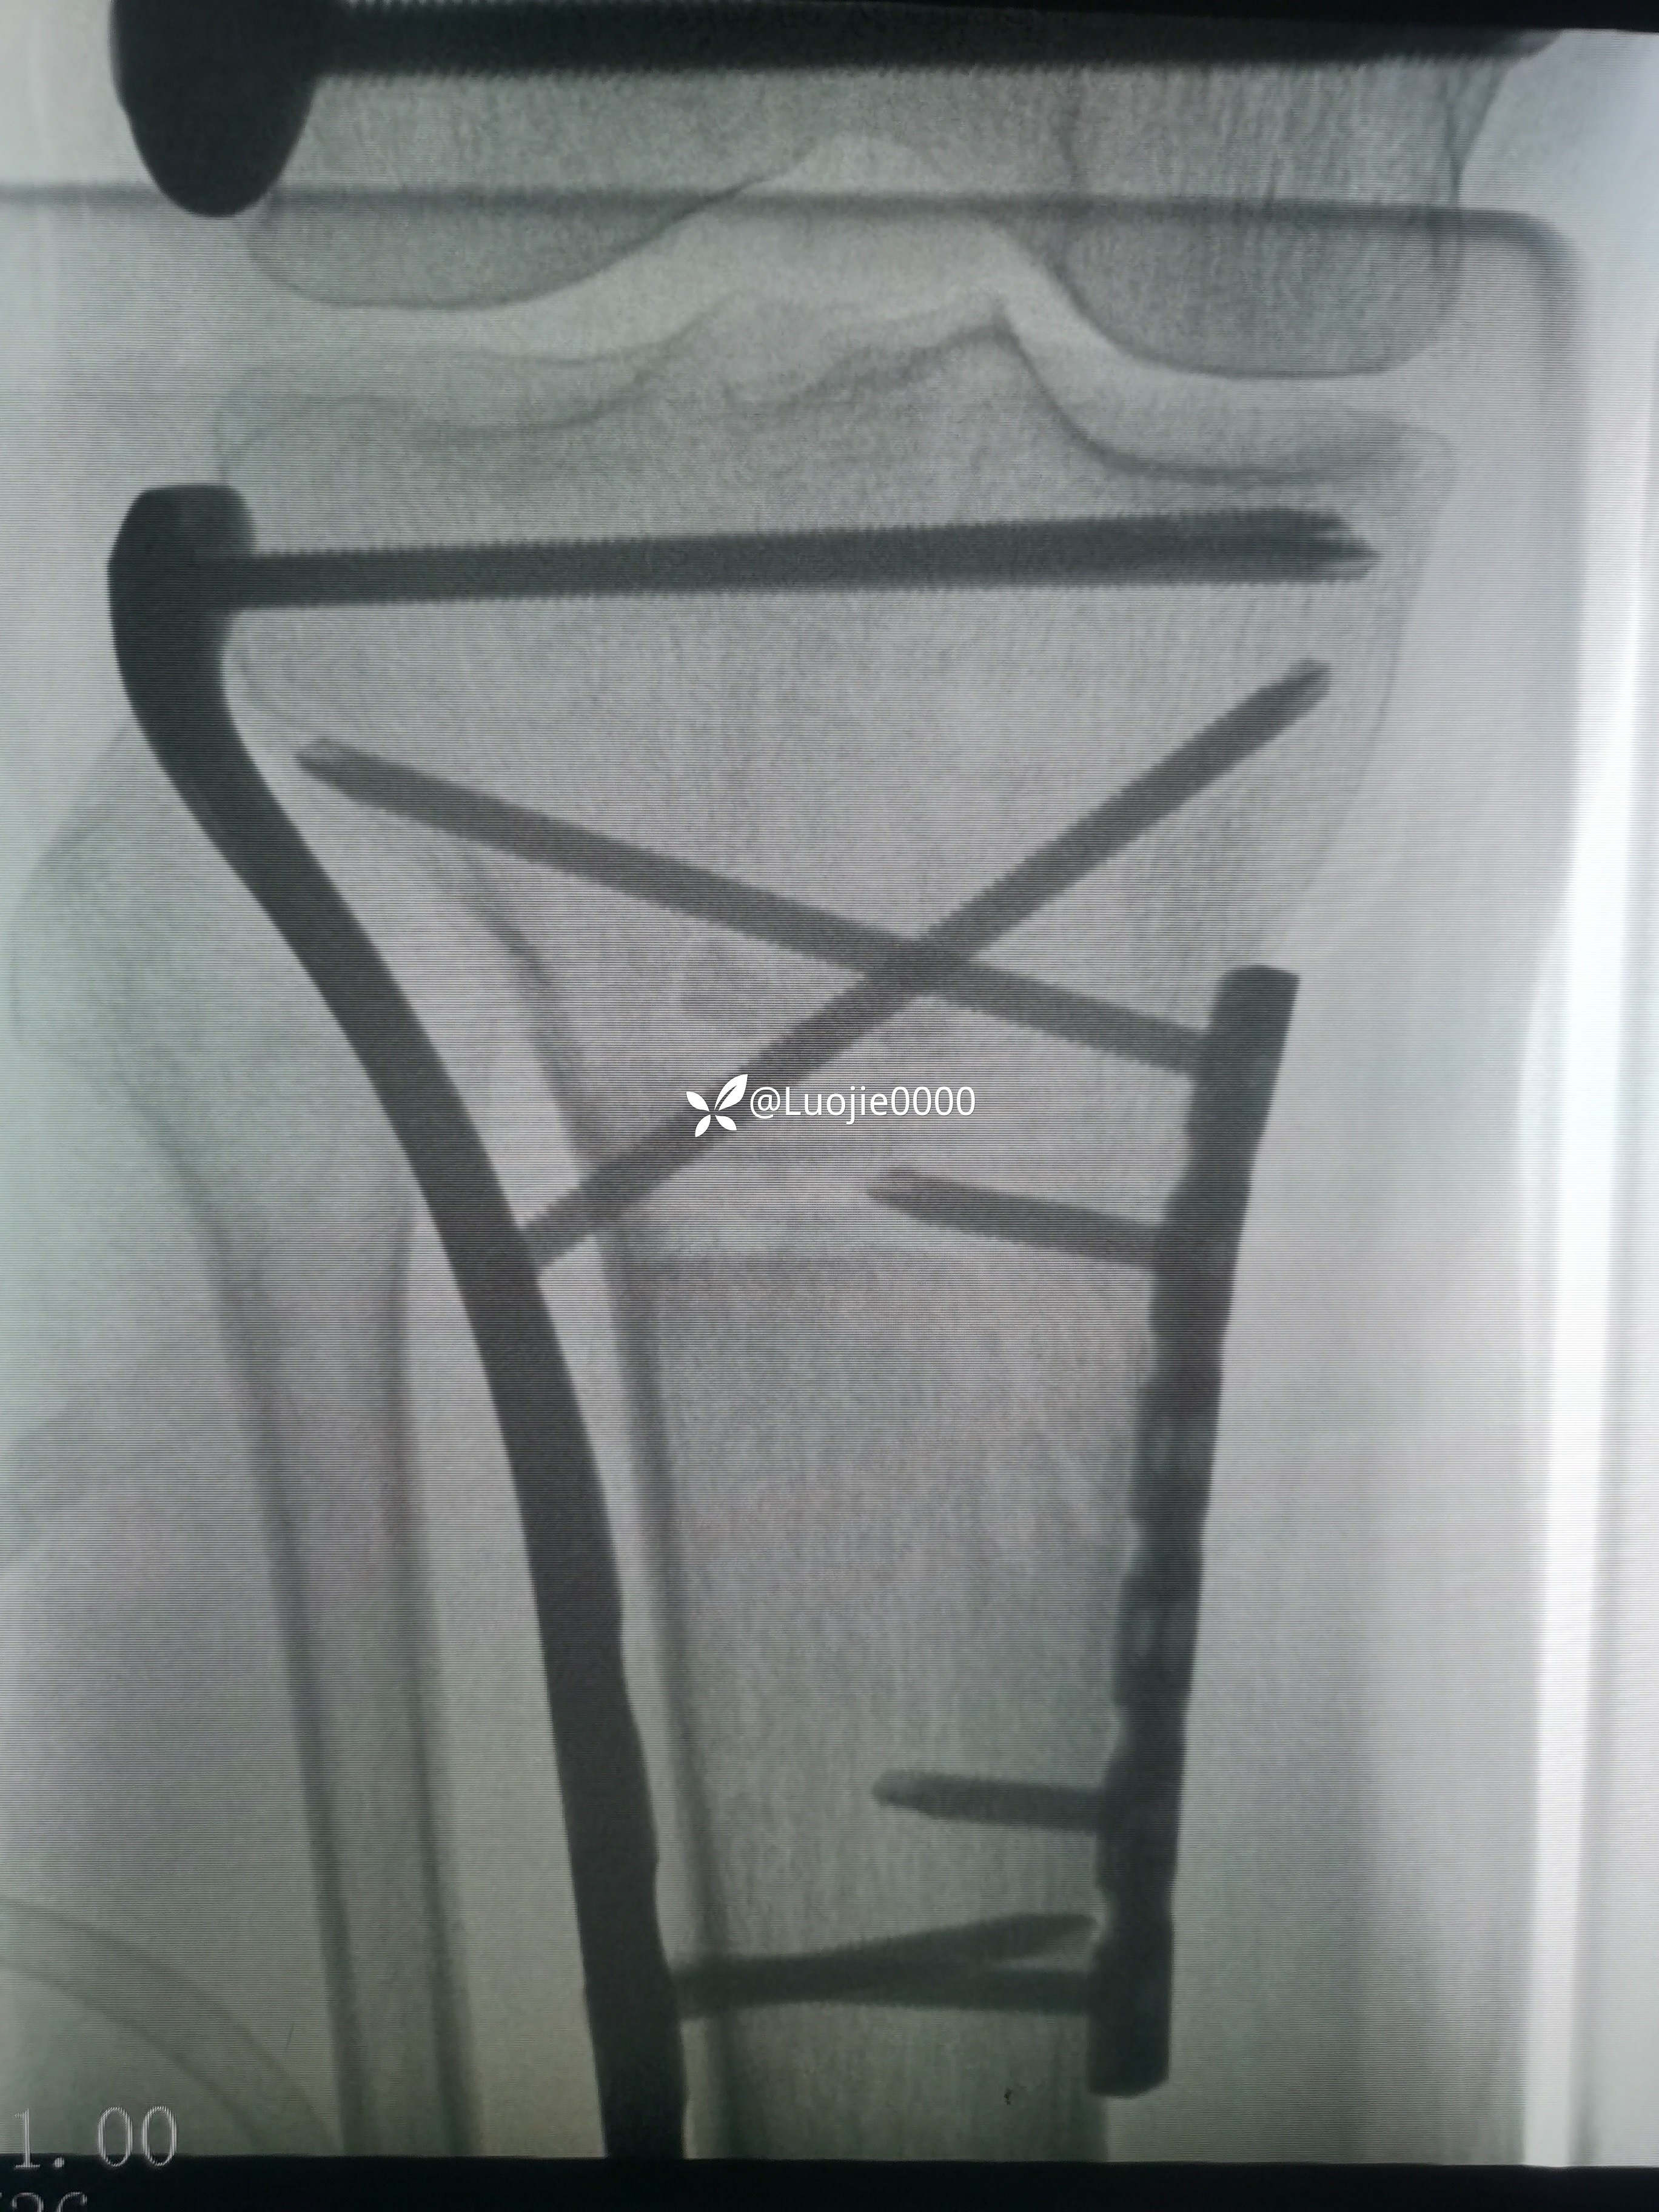

照书做没成功

切开复的位